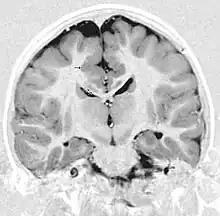

Bilateral frontoparietal polymicrogyria is a genetic disorder with autosomal recessive inheritance that causes a cortical malformation. Our brain has folds in the cortex to increase surface area called gyri and patients with polymicrogyria have an increase number of folds and smaller folds than usual.[1] Polymicrogyria is defined as a cerebral malformation of cortical development in which the normal gyral pattern of the surface of the brain is replaced by an excessive number of small, fused gyri separated by shallow sulci and abnormal cortical lamination. From ongoing research, mutation in GPR56, a member of the adhesion G protein-coupled receptor (GPCR) family, results in BFPP. These mutations are located in different regions of the protein without any evidence of a relationship between the position of the mutation and phenotypic severity.[2] It is also found that GPR56 plays a role in cortical pattering.[3]

- Radiological findings (MRI) demonstrated symmetric generalized polymicrogyria with decreasing anterior-posterior gradient, most prominent in frontoparietal cortex.[5]

- Numerous gyrus on the cortex

- Small gyri and sulci

- Thin cortex

There are different tests or methods used to determine GPR56 expression or visuals of the brain to analyze the specific sections that are affected. These tests for example, using animals such as mice, RNAi, Behavioral assay, Electron microscopy, CT scan, or MRI demonstrate different results that concludes an affected BFPP patient.[15] MRI's reveal either irregularity to the cortical surface suggestive of multiple small folds or an irregular, scalloped appearance of the gray matter-white matter junction.

Neuroimaging

The diagnosis of polymicrogyria is typically made by magnetic resonance imaging (MRI) since computed tomography (CT) and other imaging methods generally do not have high enough resolution or adequate contrast to identify the small folds that define the condition. The cerebral cortex often appears abnormally thick as well because the multiple small gyri are fused, infolded, and superimposed in appearance.[5]

Gross neuropathologic examination reveals a pattern of complex convolutions to the cerebral cortex, with miniature gyri fused and superimposed together, often resulting in an irregular brain surface. The cortical ribbon can appear excessively thick as a result of the infolding and fusion of multiple small gyri.[5]

Microscopic examination demonstrates that the cerebral cortex is in fact abnormally thin and has abnormal lamination; typically the cortex is unlayered or has four layers, in contrast to the normal six layers. The most superficial layers between adjacent small gyri appear fused, with the pia (layer of the meninges) bridging across multiple gyri. Prenatal diagnosis for BFPP is also available for pregnancies at risk if the GPR56 mutations have been identified in an affected family member.[5]